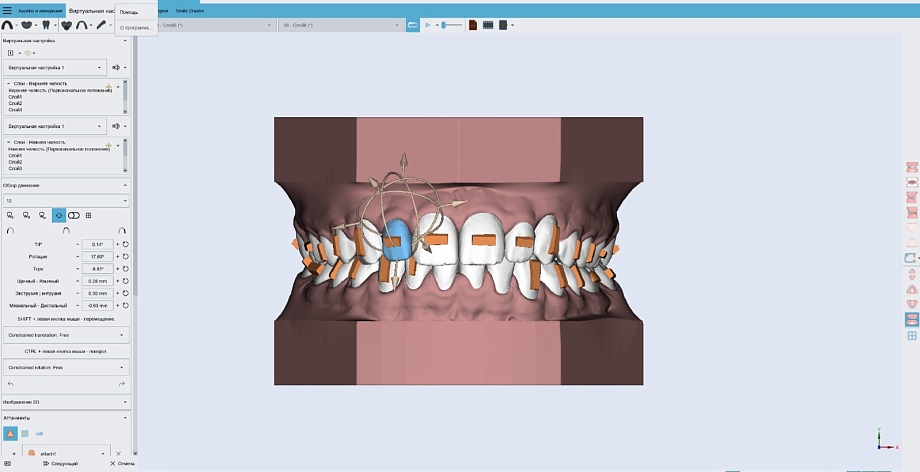

- Диагностика представляет собой несколько этапов. Диагностика состоит из статических и динамических методов исследования. Пациент сначала проходит статическую диагностику, которая включает: компьютерную томографию и теле рентгенографию позволяет определить состояние костных элементов височно-нижнечелюстного сустава и степень разрушения тканей и определить необходимые процедуры, цифровое сканирование зубов с использованием современных сканеров и фотографии позволяет получить точные данные зубных рядов для изготовления с помощью принтера 3Д моделей челюстей. К динамическим методам диагностирования относятся цифровая аксиография, которая с высокой точностью проводит запись движения ВНЧС при различных нагрузках и электромиографию, записывающую биопотенциал тонуса мышц при жевании.

Используется специализированная программа для симуляции движений челюсти и определения оптимального положения суставов. Данные загружаются и анализируются для определения необходимых коррекций, помогают найти патологии и определить утраченные параметры состояния всего зубочелюстного аппарата. Комбинация всех данных позволяет разработать точный план лечения, обеспечивая пациенту максимально оптимальные результаты в восстановлении зубочелюстной системы.

- Мы разработали цифровую окклюзионную шину, она представляет собой съемное приспособление – незаметное и изготовленное из прозрачного материала. Изготавливают ее с помощью CAD/CAM технологии - это компьютерные программы для моделирования конструкции шины и высокоточное фрезерное пяти осное оборудования для изготовления внутриротового аппарата из современного медицинского полимера. В свое время мы проводили ряд исследований со всеми окклюзиоными шинами, которые присутствуют в стоматологическом мире. И цифровая окклюзионная шина нашего производства показала, что она в 2,5 раза эффективнее своих предшественников. Соответственно, использование этой шины помогает восстановить положение нижней челюсти в ту позицию, которая у пациента была утрачена.

В наших клиниках результаты гнатологического исследования применяются в обязательном порядке при ортодонтическом лечении, направленном на выравнивание зубов и исправление прикуса. Элайнеры - современная альтернатива брекетам, пользуются большой популярностью. Этот передовой цифровой метод восстановления положения зубов обеспечивает высокие результаты и сокращенные сроки лечения. После восстановления проводится цифровой анализ зубного ряда, если пациенту необходимо восстановить объем зубов, мы используем керамические реставрации. Самое главное, срок службы таких реставраций, как мы говорили ранее, составляет 20−30 лет.